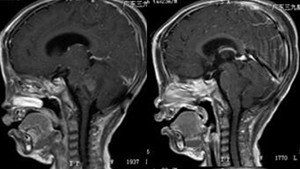

▲术后